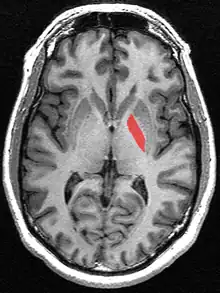

![]() Globus pallidus (in red) shown within the brain | |

The globus pallidus (GP), also known as paleostriatum or dorsal pallidum,[1] is a major component of the subcortical basal ganglia in the brain. It consists of two adjacent segments, one external (or lateral), known in rodents simply as the globus pallidus, and one internal (or medial). It is part of the telencephalon, but retains close functional ties with the subthalamus in the diencephalon – both of which are part of the extrapyramidal motor system.[2]

In primates, the globus pallidus is divided into two parts by a thin medial medullary lamina.[7] These are the internal globus pallidus (GPi) and the external globus pallidus (GPe); both are composed of closed nuclei surrounded by myelinic walls.

The globus pallidus is a structure in the brain involved in the regulation of voluntary movement.[8] It is part of the basal ganglia, which, among many other functions, regulate movements that occur on the subconscious level.